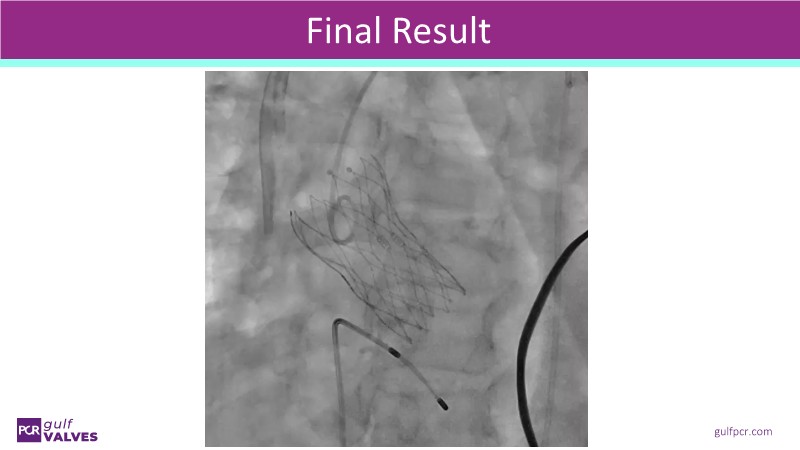

Discover a selection of cases showcasing the key features of the Navitor Valve System and its clinical applications. This session explores auxiliary access, the use of Navitor in alternative access and complex PCI, its performance in challenging peripheral anatomies, and innovative outcomes with the Vantage 30D system.